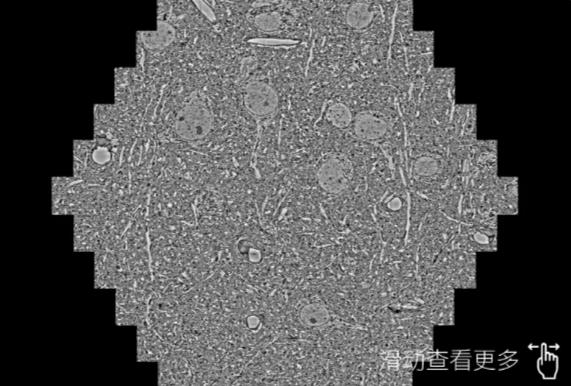

鼠脑切片。左图使用博尔塔拉蔡司博尔塔拉扫描电镜MultiSEM706对165μmx143pm面积区域成像,耗时仅需1.5秒。右图为鼠脑切片中30μm区域放大效果。样品由芝加哥大学B.Kasthuri提供。